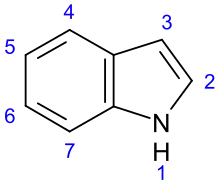

Indole derivatives[100]

Non-isoprene indole alkaloids | ||

| Simple indole derivatives [125] | Tryptophan → tryptamine or 5-Hydroxytryptophan[126] | Serotonin, psilocybin, dimethyltryptamine (DMT), bufotenin[127][128] | |

| Simple derivatives of β-carboline[129] | Harman, harmine, harmaline, eleagnine [125] | ||

| Pyrroloindole alkaloids [130] | Physostigmine (eserine), etheramine, physovenine, eptastigmine[130] | ||

| Semiterpenoid indole alkaloids | |||

| Ergot alkaloids[100] | Tryptophan → chanoclavine → agroclavine → elimoclavine → paspalic acid → lysergic acid[130] | Ergotamine, ergobasine, ergosine[131] | |

| Monoterpenoid indole alkaloids | |||

| Corynanthe type alkaloids[126] | Tryptophan → tryptamine → strictosidine (with secologanin) [126] | Ajmalicine, sarpagine, vobasine, ajmaline, yohimbine, reserpine, mitragynine,[132][133] group strychnine and (Strychnine brucine, aquamicine, vomicine[134]) | |

| Iboga-type alkaloids[126] | Ibogamine, ibogaine, voacangine[126] | ||

| Aspidosperma-type alkaloids[126] | Vincamine, vinca alkaloids,[27][135] vincotine, aspidospermine[136][137] | ||